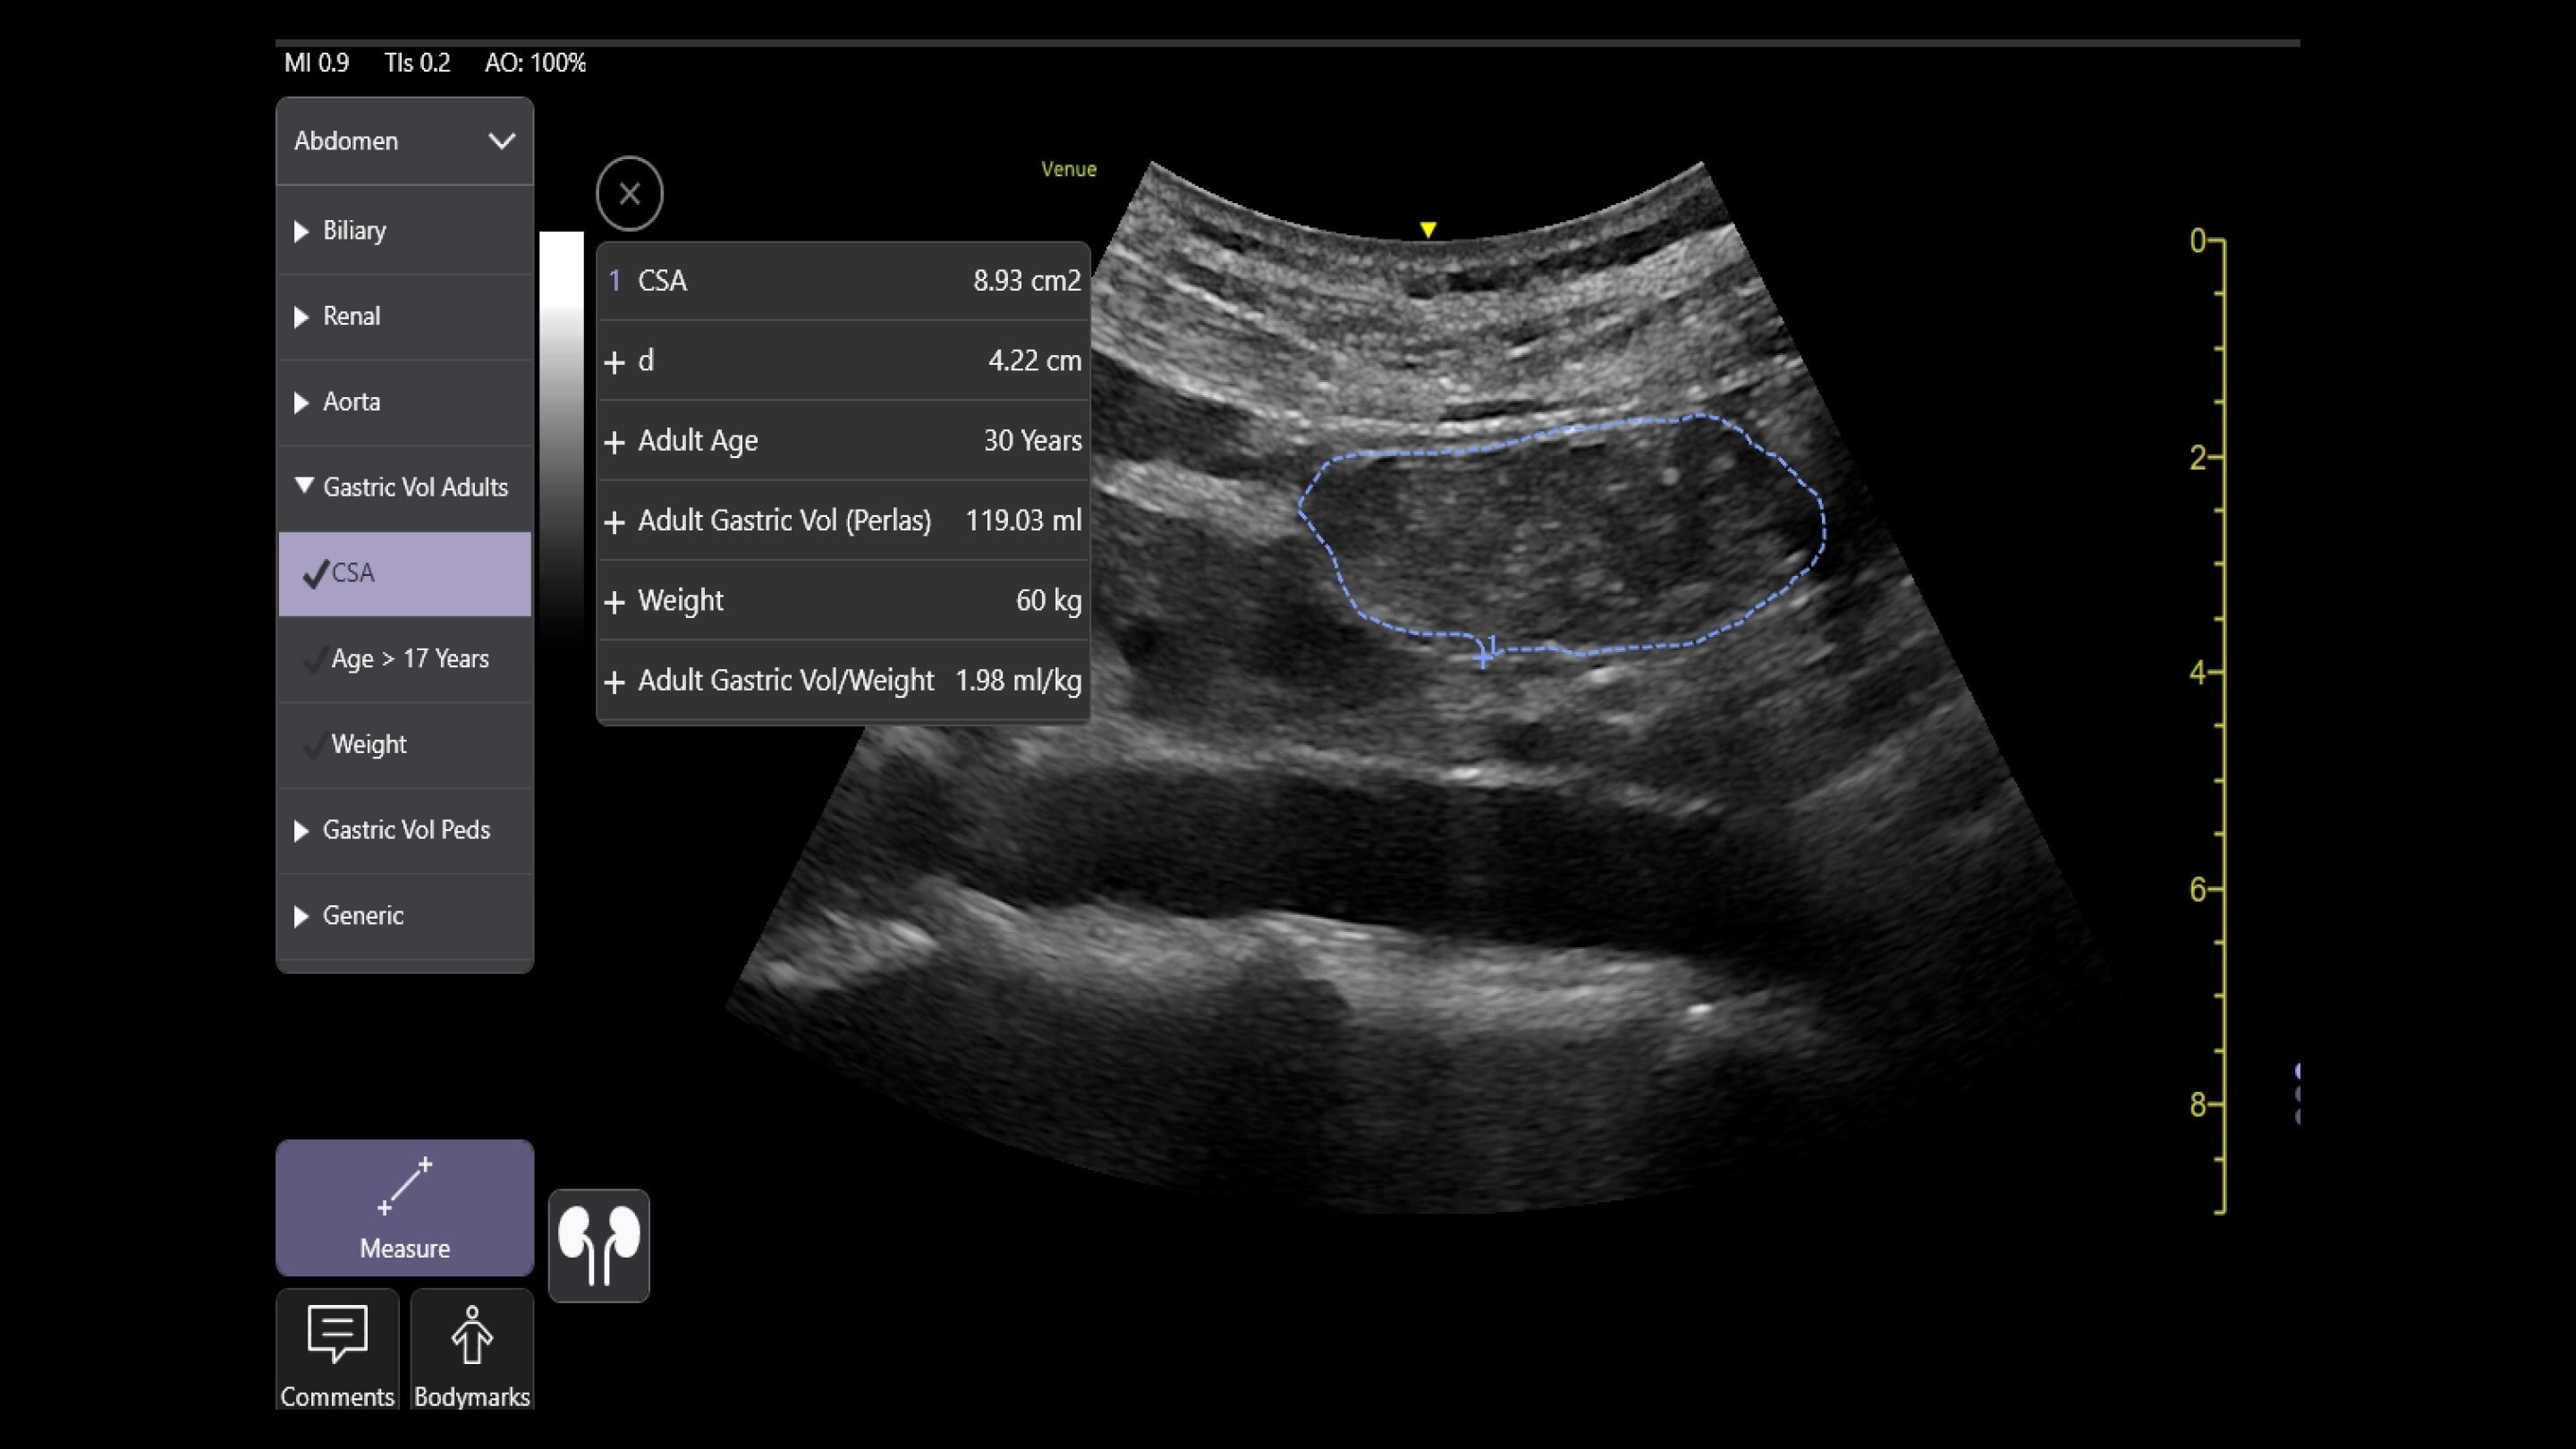

Wireless probe integration

Sync up and go - without wires you’re not tethered to a system or a space

Small yet powerful

Flexible, wireless dual-probes deliver clear images and Venue family software